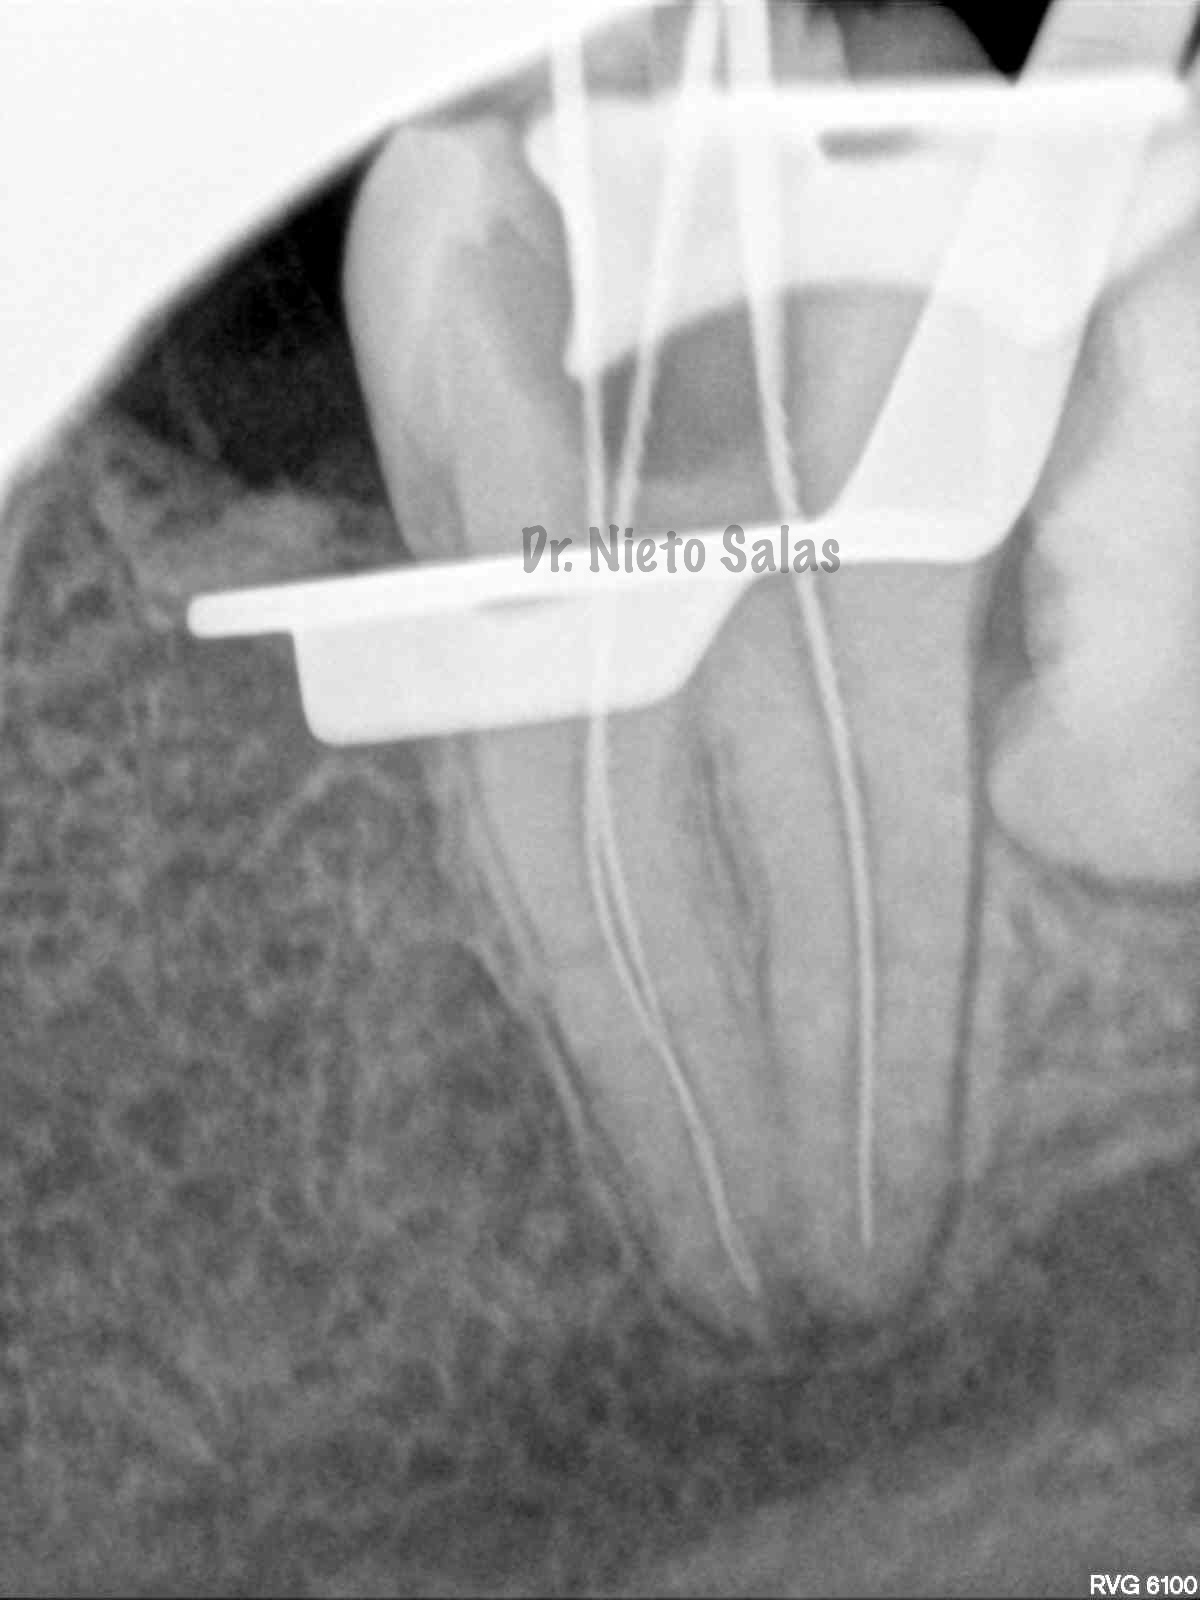

Intentamos mantener la permeabilidad y la forma de  los conductos. Instrumentamos con Pathfile y Mtwo hasta un 25-6%.

(ORTO)                                                               (DISTO)

(MESIO)